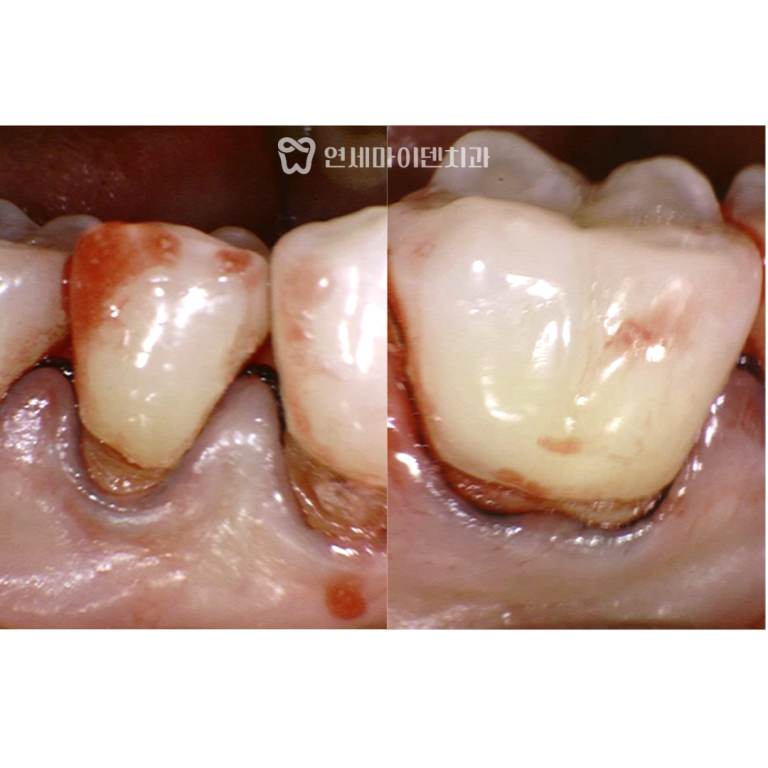

임플란트 공간이 부족했던 초기 상태

해당 환자분은 오른쪽 아래 6번 어금니를

오래전에 발치하신 분으로,

그 결과 뒤쪽의 7번 어금니와 8번 사랑니가

앞으로 기울어져 있었습니다.

이로 인해 임플란트를 식립할 공간이 부족한 상태였고,

보철만으로는 치료가 불가능했습니다.

부분교정 3개월 경과

교정 초반에는 부드럽고 얇은 와이어를 사용해

치열의 기본 정렬을 유도했습니다.

이후에는 쓰러진 7번 어금니를 세우기 위해

특수 제작된 접은 철사와 코일 스프링을 병행했습니다.

일반적인 일자 철사 대신,

치아를 원하는 방향으로 정교하게 이동시키기 위해

맞춤형 와이어를 적용했습니다.

3개월 경과 시점에서는

점점 어금니가 세워지며, 임플란트 공간이

서서히 확보되는 변화가 확인되었습니다.